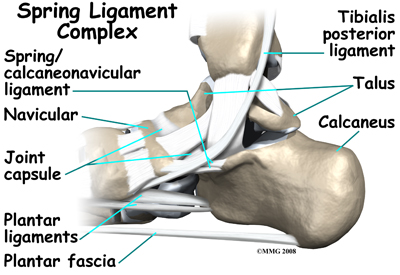

Many small ligaments hold the bones of the foot together. Most of these ligaments form part of the joint capsule around each of the joints of the foot. A joint capsule is a watertight sac that forms around all synovial-type joints. The capsule is made up of the ligaments around the joint and the soft tissues between the ligaments that fill in the gaps and form the sac.

The spring ligament complex is often involved in AAFD. This group of ligaments supports the talonavicular joint. The spring ligament complex works with the posterior tibial tendon and the plantar fascia to support and stabilize the longitudinal arch of the foot.